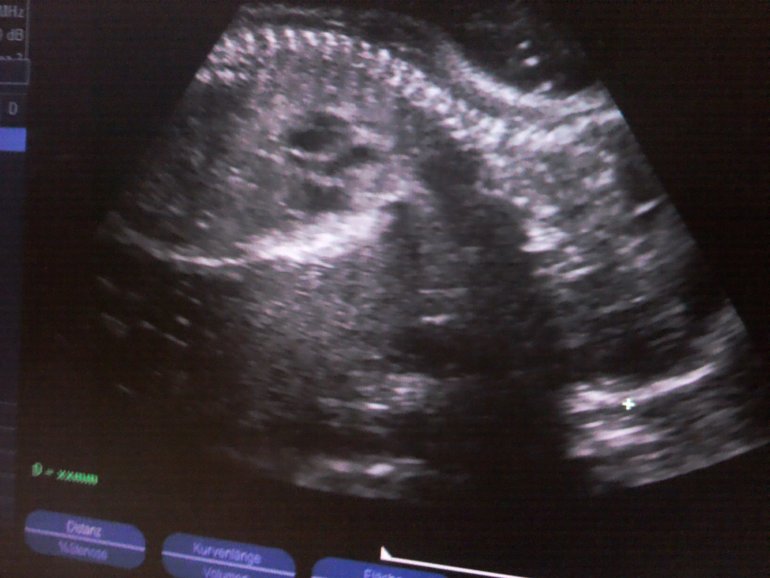

Еще вчера мы были на Узи,слава богу у нас все хорошо.

Показали мне сердечка,каждый из 4 отсеков прослушали,показали мозг,позвоночник,лопатки,плечики,коленки,ребрышки,пальчики на ручках и ножках)В общем отклонений не выявлено,могу спать спокойно)У нас так и осталось обвитие пуповинкой,но сказали,что оно легкое,как шарфик.Положение плода поперечное,ножками как раз мне в ребра бьет)

На узи он такой большой уже)))

УЗИ